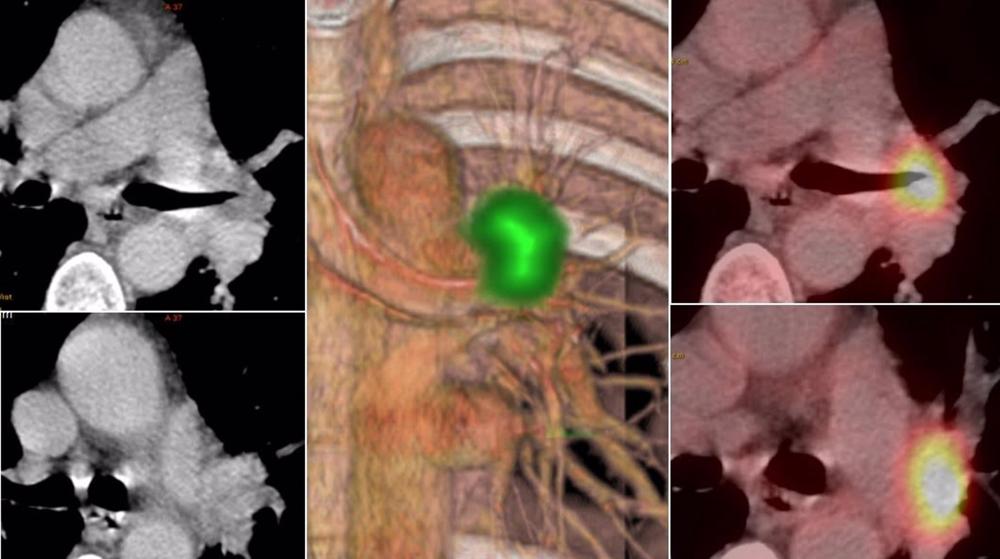

El Hospital La Luz aboga por el uso al cien por cien de la tecnología PET-CT entre médicos nucleares y radiólogos, ya que es una técnica que consiste en una exploración fundamental en el manejo del paciente oncológico, especialmente en aquellos casos de tumores agresivos y de gran prevalencia a nivel de la población española como es el caso del cáncer de pulmón, mama, colon, linfomas y melanomas entre otros.

Según el jefe de Departamentos de Medicina Nuclear e Imagen Molecular del Hospital Universitario La Luz y del Hospital Universitario Quirónsalud Madrid, Antonio Maldonado, la ’’inmensa mayoría’’ de los servicios focalizan los estudios únicamente en la vertiente PET, sin considerar la ’’valiosa información’’ que puede proporcionar la imagen morfológica CT.

’’El radiólogo apenas participa en la interpretación de estos estudios, sacando conclusiones básicamente de la información metabólica y de forma escasa de la morfológica del CT. Pocos son los radiólogos que colaboran estrechamente con los médicos nucleares en la confección de los informes de los estudios PET-CT, con la consiguiente y lógica perdida de información que el CT puede proporcionar’’, ha dicho Maldonado.

Por ello, el Departamento de Medicina Nuclear e Imagen Molecular del Hospital Universitario La Luz y del Hospital Universitario Quirónsalud Madrid, lidera el uso al cien por cien de la tecnología PET-CT entre los médicos nucleares y radiólogos. ’’Desde que empecé a realizar estudios PET-CT, me di cuenta de la importancia que suponía el trabajo conjunto de ambos especialistas en el rendimiento final de la prueba PET-CT y los enormes beneficios que podíamos aportar tanto al médico como al paciente si usábamos todos los recursos a nuestro alcance’’, ha enfatizado el doctor Maldonado.

Asimismo, el experto ha explicado que desde 2003 (fecha de la introducción de la PET-CT en España) ha liderado proyectos PET-CT donde han colaborado los especialistas de Medicina Nuclear y Radiodiagnóstico en la realización de estas pruebas de imagen médica. ’’Aspectos tan importantes como el uso de protocolos CT diagnósticos, la realización de un único informe mixto metabólico/morfológico y conclusiones prácticas e integradas que solucionen las preguntas de los oncólogos son las piezas claves de nuestra forma de actuar’’, ha argumentado.

Se evitan, prosigue, pruebas radiológicas innecesarias, hacemos de cada estudio una pequeña sesión clínica médico nuclear/radiólogo, intentando dar la mejor respuesta clínica a los médicos que piden las pruebas. Las conclusiones de los informes poseen una ’’gran orientación clínica’’ e intentan servir de ayuda en la toma de decisiones en el manejo del paciente oncológico.